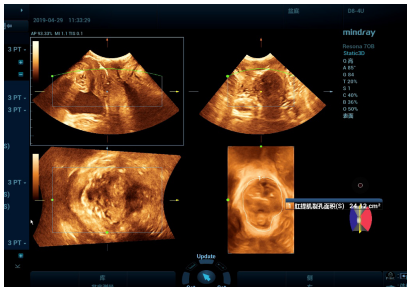

(二)三维盆底彩超检查

盆腔器官脱垂主要是由于分娩损伤,长期慢性咳嗽、便秘、下蹲时间过长至腹压增高等因素导致。特别是绝经后女性雌激素水平减低、盆底组织萎缩退化而薄弱,可导致盆底肌肉松弛。通过三维盆底超声技术可以直观显示女性盆腔器官有无脱垂以及观察盆底结构、肛提肌裂孔形态和大小的变化,以获取诊断信息,制定治疗方案。

阿坝州人民医院超声科引进了两台四维彩色多普勒超声诊断仪,目前已有近300名女性患者做了盆底三维彩超检查,阳性率达70%以上。